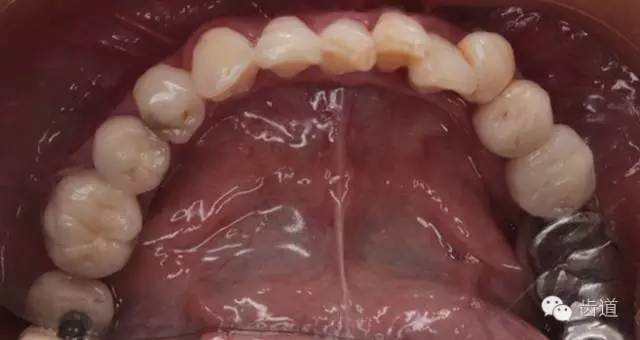

2、上頜牙合面觀

3、下頜牙合面觀